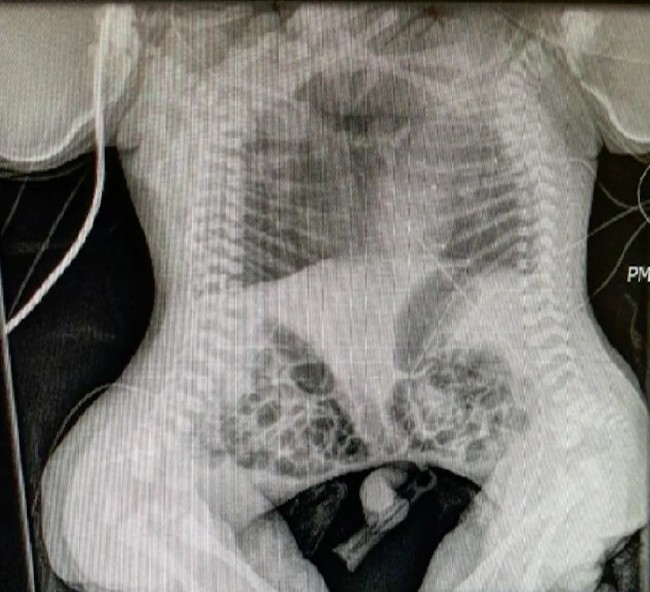

Kalbinden yapışık ikizler

İlk ultrason kontrolünde ikizlerin kalbi ortak çalıştığını fark eden doktorlar, siyam ikizlerin yaşamalarının imkansız olduğunu söyledi. İkizlerini her ne pahasına olursa olsun doğurmaya karar veren anne Phillip, bebeklerini ameliyat ettirmek için uygun bir doktor arayışına girdi. Tüm risklere rağmen kalbi ortak çalışan siyam ikizleri doktorlar tarafından başarılı bir şekilde ameliyat edildi. İşte o mucizevi siyam ikizleri...